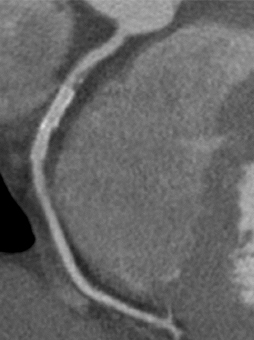

a. 心臓CT

SPECT/CT融合画像

図3 労作性狭心症症例。後側壁〜後下壁の心筋虚血はLCXおよびRCA両方の有意狭窄による。